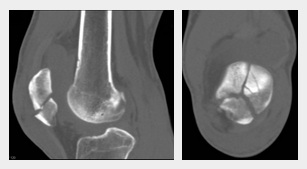

Wenn das Röntgenbild nicht ausreicht bzw. der Bruch auf dem Röntgenbild nicht sichtbar ist, wird noch ein CT gemacht, selten noch ein MRT (1'22''). Dann sieht man die Details. Der Bruch der Kniescheibe kann sein

-- ein Teilabriss

-- ein Querbruch

-- ein Längsbruch (1'32'') [web03].

Diverse Brüche der Kniescheibe,

Sammelfoto: Abrissfraktur, Querfraktur, Längsfraktur,

Sternfraktur

Diverse Brüche der Kniescheibe, Sammelfoto: Abrissfraktur, Querfraktur, Längsfraktur, Sternfraktur [7]

Bruch der Kniescheibe als

Sternbruch, Röntgenfotos

Bruch der Kniescheibe als Sternbruch, Röntgenfoto [8]

Ausserdem wird noch unterschieden, ob der Bruch "verschoben" oder "nicht verschoben" ist (1'36'') [web03].